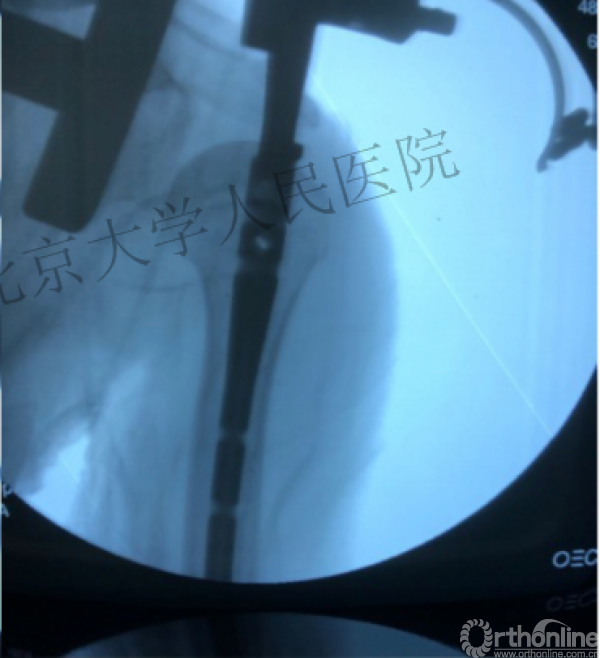

进钉更完美——我们的帮助

术中片

可否有更好的进钉和复位的更好帮助办法?